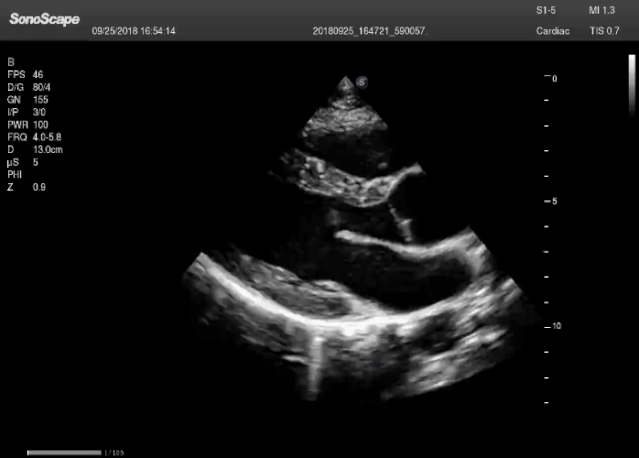

左室长轴

(2)摇:整个超声探头平面紧贴受检区域皮肤,以超声探头与胸壁的接触点为支点,将超声探头左右摇摆,观察整个切面。